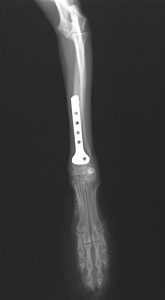

術後X線所見です。術後は安静を保ち、徐々に運動量を増やしていきます。本症例は骨癒合が順調に進みましたが、プレート下の骨にやや骨粗鬆が認められたため、段階的にインプラントの抜去を行ないました。

術後5ヵ月で骨粗鬆も改善したため、インプラントを全て抜去し完治しました。

本症例は橈骨の骨幅がわずか4.5mmしかないため、設置するプレート、スクリューは極小のものになり、やり直しがきかず難易度はかなり高くなります。